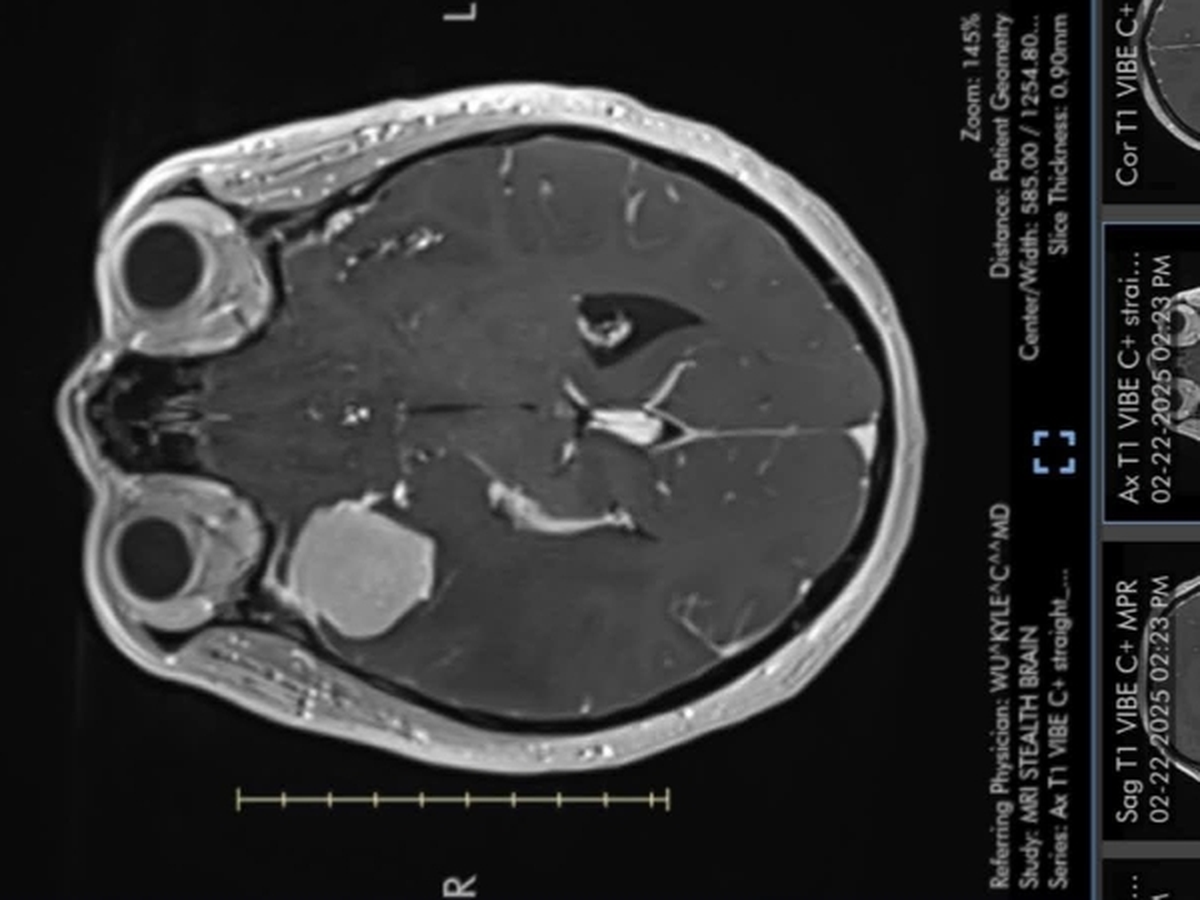

In November 2024, my mother began experiencing auras, the subtle signals your body provides before the onset of a seizure. By early February 2025, she suffered her first actual seizure. Although she was prescribed medication, she continued to struggle with debilitating headaches and excruciating eye pain. On February 21, in desperation due to the persistent pain, she visited the emergency room. After undergoing an MRI, we received devastating news: a large tumor, the size of a golf ball, was pressing on the lining of her brain, obstructing her carotid artery and optic nerve. She was promptly rushed to OSU and underwent emergency surgery on February 23. It was later confirmed that the tumor was a meningioma.